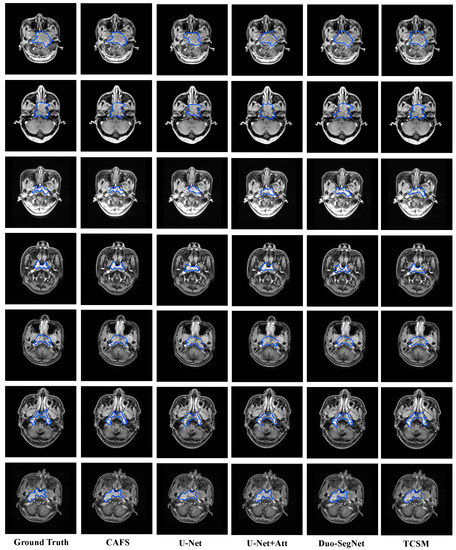

5.3. Comparison with State-of-the-Art Models

| Model | DSC | Jaccard | Precision | Recall |

|---|---|---|---|---|

| CAFS | 0.8723 | 0.7964 | 0.8849 | 0.8796 |

| U-Net [39] | 0.7456 | 0.6868 | 0.6569 | 0.8822 |

| U-Net + Att | 0.8198 | 0.7011 | 0.8202 | 0.8309 |

| Duo-SegNet [66] | 0.8130 | 0.6849 | 0.7966 | 0.8307 |

| TCSM [67] | 0.7970 | 0.6987 | 0.8014 | 0.8978 |